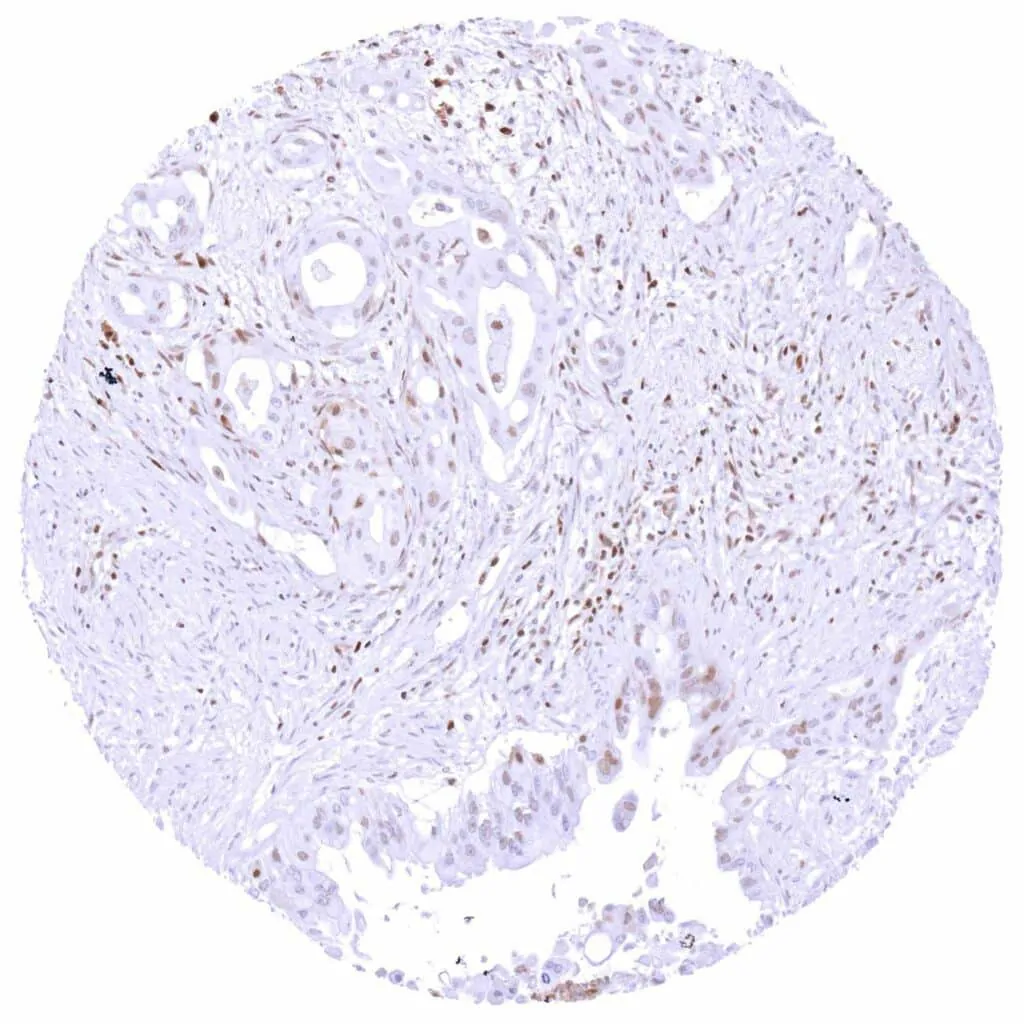

Pancreas – Ductal adenocarcinoma with weak to moderate, predominantly nuclear p27 staining of few tumor cells.

Prostate – Adenocarcinoma (Gleason 3+3=6) with moderate to strong, predominantly nuclear p27 positivity of tumor cells.

Prostate – Adenocarcinoma (Gleason 5+5=10) with a variable, weak to strong nuclear and cytoplasmic p27 staining of tumor cells.

Prostate: Adenocarcinoma (Gleason 4+4=8) with strong p27 immunostaining of tumor cells.